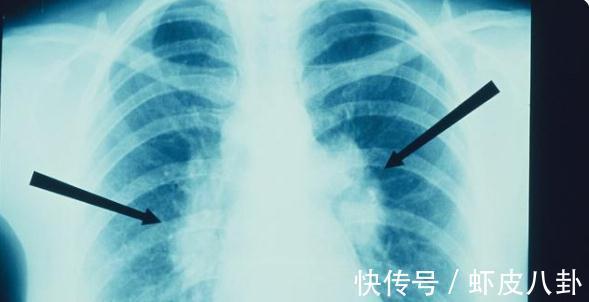

乳腺结节是女性查体中常见的诊断,除了上文中提到的结节的大小、活动度、边缘、生长速度外,还要结合患病的年龄及症状来看。

比如结节随着例假有所变化,那么多为乳腺增生,如果为初产妇且伴有疼痛,往往为炎症结节,除此之外乳腺结节同样适用TI-RADS分级,根据分级再来选择处理方法,对于4级以下的患者,可进行定期随访,4级可进行穿刺活检,若为恶性则手术治疗,5级及以上直接进行手术。